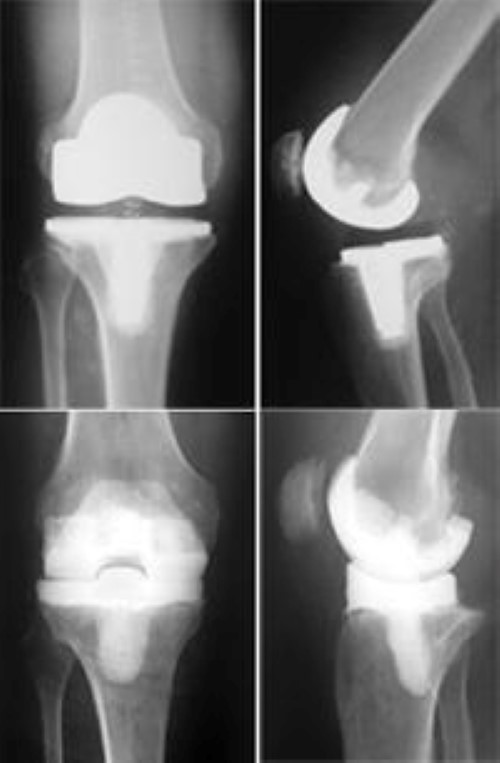

AntibioticLoaded Cement Articulating Spacer for 2Stage Reimplantation Antibiotics For Infected Knee Replacement The approach depends on the timing. Plan the appropriate use of antibiotic bone cement prior to surgery: Antibiotics are given within 1. The most important known measures to lower the risk of infection after total joint replacement include: Overview— in general, management of pjis consists of surgery and antimicrobial therapy. Antibiotics before and after surgery. Antibiotics For Infected Knee Replacement.

AntibioticLoaded Cement Articulating Spacer for 2Stage Reimplantation Antibiotics For Infected Knee Replacement Antibiotics are given within 1. Plan the appropriate use of antibiotic bone cement prior to surgery: Antibiotics before and after surgery. Overview— in general, management of pjis consists of surgery and antimicrobial therapy. The approach depends on the timing. The most important known measures to lower the risk of infection after total joint replacement include: Antibiotics For Infected Knee Replacement.